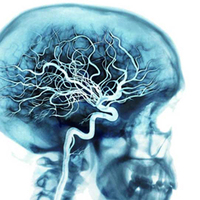

Kalp ve Damar Cerrahisi Uzmanı Doç. Dr. Gökçe Şirin, yaptığı yazılı açıklamada, halk dilinde "balonlaşma" olarak bilinen anevrizmanın, damar duvarının sağlamlığını kaybetmesi ve genişlemesi olduğunu anlattı.

AA'nın haberine göre; bir genişleme ya da anevrizmadan söz edebilmek için normal damar çapının en az 1,5-2 katı kadar genişlemesi gerektiğini belirten Şirin, kişinin yaşına, cinsiyetine, boyuna, vücut ağırlığına ve bulunduğu bölgeye göre damar çaplarının farklılık gösterdiğini hatırlattı.

Doç. Dr. Şirin, şunları kaydetti: "Anevrizmalar genellikle herhangi bir belirti vermez. Çoğu anevrizma rastlantısal olarak başka bir nedenle yapılan muayenenin bir bulgusu olarak saptanır. Yakınmalar, anevrizmanın bulunduğu yere göre farklılık göstermektedir. Karın içerisinde yerleşen anevrizmalar karın ağrısı veya sıklıkla bele doğru yayılan ağrı ile ortaya çıkmaktadır. Büyük anevrizmalarda hasta elini karnına koyduğunda eline bir top vuruyormuş gibi hissedebilir. Göğüs boşluğundaki anevrizmalar ise göğüs ağrısı, sırta vuran ağrı veya ses kısıklığına neden olabilir. Bazen de ilk bulgu aort damarının yırtılması şeklinde olmaktadır."

Ultrasonografi ile anevrizmanın çok kolay teşhis edilebildiğini aktaran Şirin, hasta takibinde ve tedavi planlanmasında ileri tetkik olarak bilgisayarlı tomografi kullanıldığını anlattı.